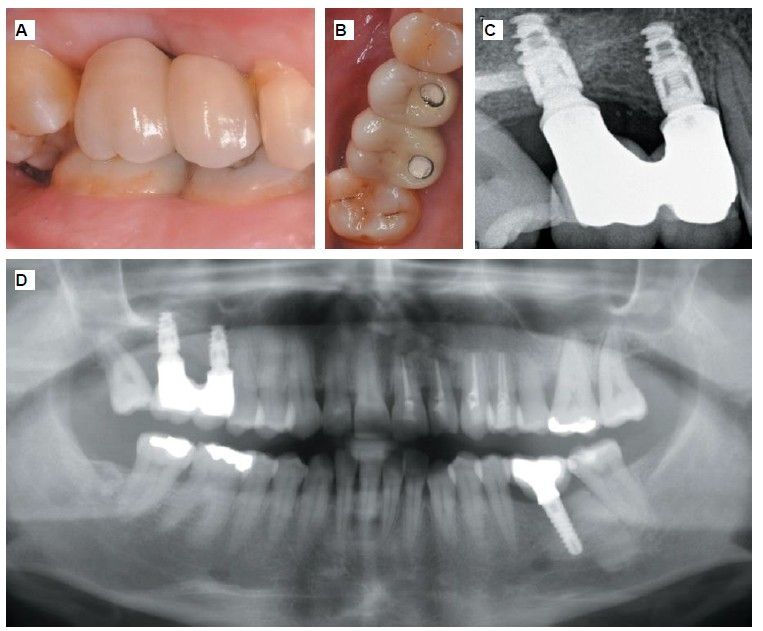

Fifteen days after the second stage, impressions were taken for the fabrication of two splinted cement-screw-retained crowns on titanium bases, with the fit verified by a parallelised periapical radiograph (Figure 10). Six months after placement of the restoration, a clinical and radiographic review was conducted, noting the favourable condition of the soft tissues (Figure 11).